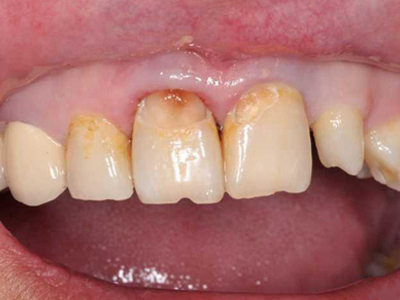

酸蚀症牙齿缺损有洞图

患酸蚀症时,牙齿可发生缺损,表现为牙列内侧有凹陷的坑洞形成,形状不规则,大小不一,坑洞处牙齿发黄,需积极控制病因,并进行充填修复治疗。